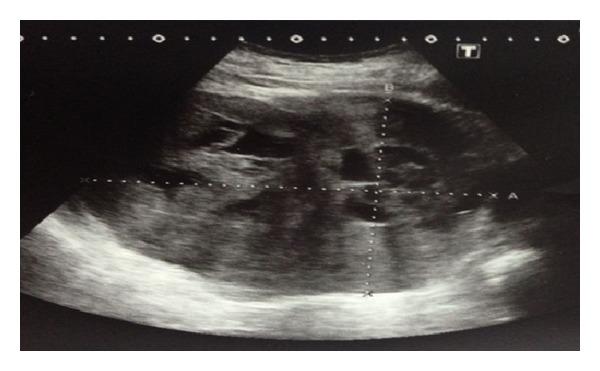

Pheochromocytoma is a rare and usually benign neuroendocrine neoplasm. Only 10% of all these tumors are malignant and there are no definitive histological or cytological criteria of malignancy. Single malignancy criteria are the presence of advanced locoregional disease or metastases. We report a case, with a giant retroperitoneal tumor having multiple metastases including palpable rib metastases, who was diagnosed as a malignant pheochromocytoma. The patient was treated with surgery. The literature was reviewed to evaluate tumor features and current diagnostic and therapeutic approaches for patients with metastatic or potentially malignant pheochromocytoma.